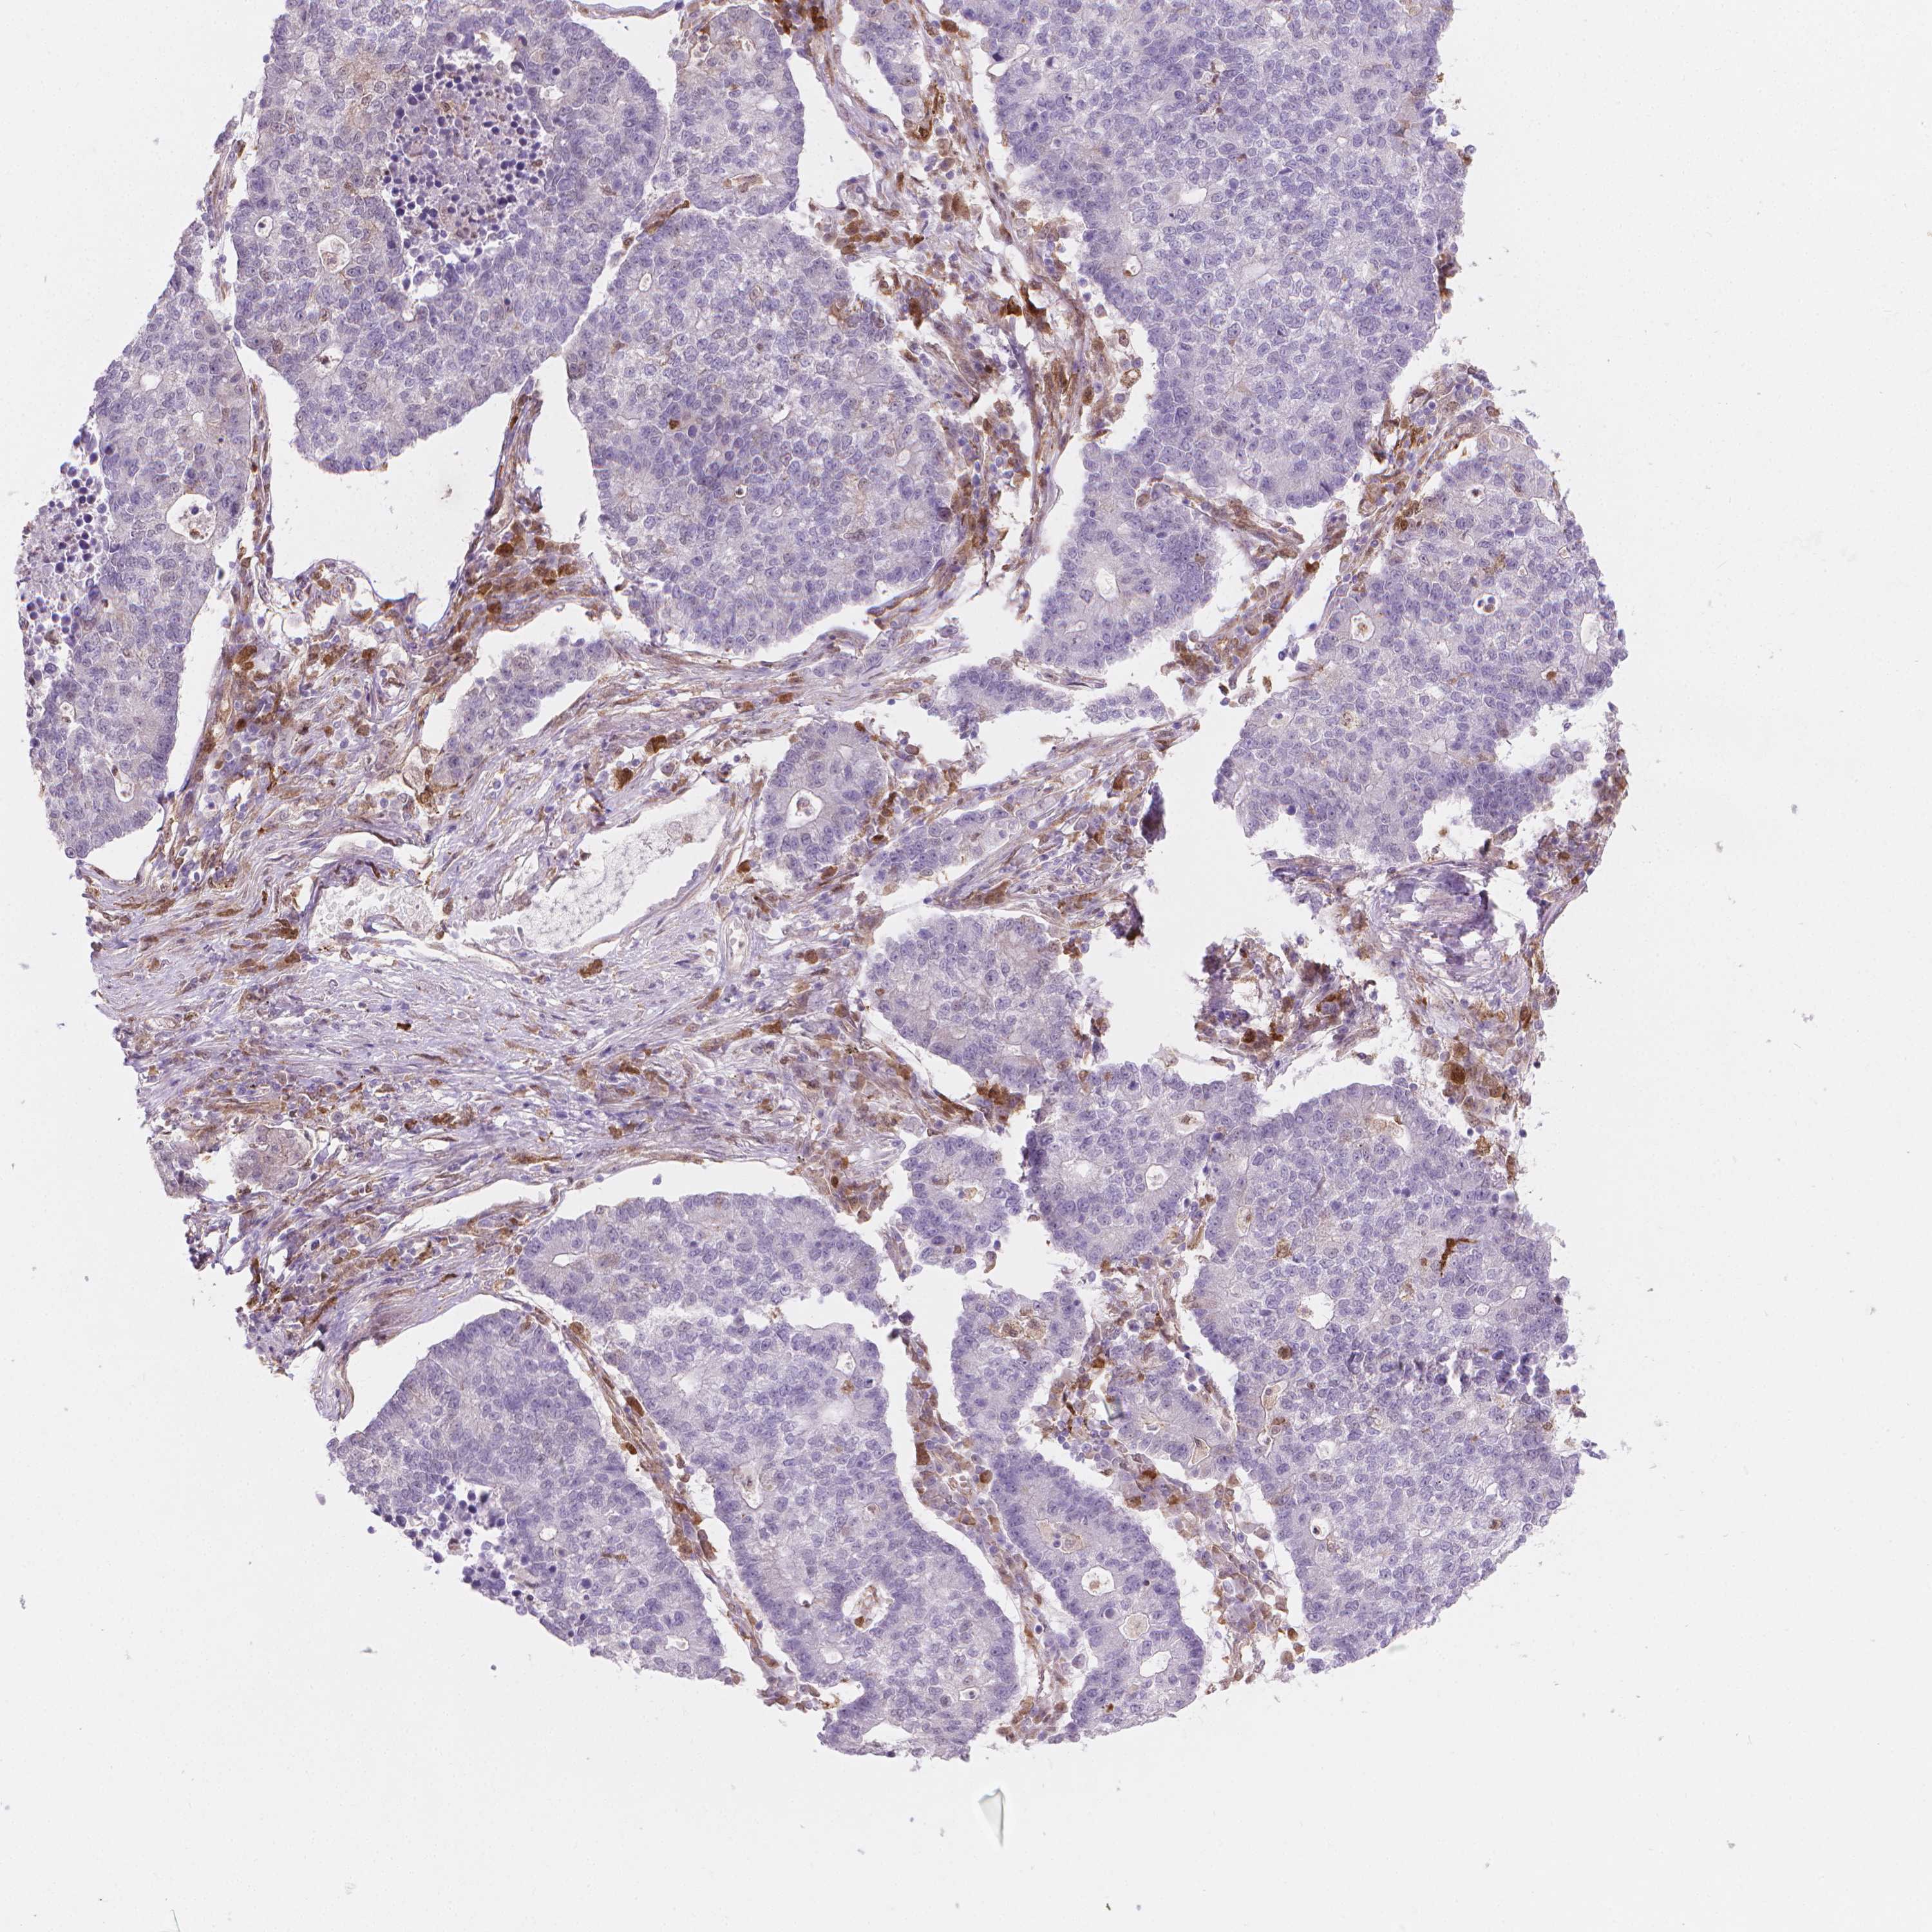

LUNG SQUAMOUS CELL CARCINOMA (TCGA) - Interactive survival scatter ploti

The Survival Scatter plot shows the clinical status (i.e. dead or alive) for all individuals in the patient cohort, based on the same data that underlies the corresponding Kaplan-Meier plots. Patients that are alive at last time for follow-up are shown in blue and patients who have died during the study are shown in red.

The x-axis shows the expression levels (FPKM) of the investigated gene in the tumor tissue at the time of diagnosis. The y-axis shows the follow-up time after diagnosis (years). Both axes are complimented with kernel density curves demonstrating the data density over the axes. The top density plot shows the expression levels (FPKM) distribution among dead (red) and alive patients (blue). The right density plot shows the data density of the survived years of dead patients with high and low expression levels respectively, stratified using the cutoff indicated by the vertical dashed line through the Survival Scatter plot. This cutoff is automatically defined based on the FPKM cutoff that minimizes the p-score. The cutoff can be changed by dragging the vertical line or by entering a cutoff value in the square labeled "Current cut-off".

Under the Survival Scatter plot the p-score landscape (black curve; left axis) is shown together with dead median separation (red curve; right axis). Dead median separation is the difference in median mRNA expression between patients who have died with high and low expression, respectively. It is calculated as follows: median FPKM expression of dead patients with high expression - median FPKM expression of dead patients with low expression. This is intended to aid the user in visually exploring custom cutoffs and the associated p-scores and dead median separation.

Individual patient data is displayed and can be filtered by clicking on one or more of the category buttons on the top of the page. Categories describing expression level and patient information include: high, low, alive, dead, female, male and tumor stages. The scale of the x-axis can be toggled between linear and log-scale by clicking on the "x log" button. Mouse-over function shows TCGA ID, patient information and mRNA expression (FPKM) for each patient.

& Survival analysisi

Kaplan-Meier plots summarize results from analysis of correlation between mRNA expression level and patient survival. Patients were divided based on level of expression into one of the two groups "low" (under cut off) or "high" (over cut off). X-axis shows time for survival (years) and y-axis shows the probability of survival, where 1.0 corresponds to 100 percent.

TNFAIP2 is not prognostic in Lung Squamous Cell Carcinoma (TCGA)

Best expression cut offi

Based on the FPKM value of each gene, patients were classified into two groups and association between prognosis (survival) and gene expression (FPKM) was examined. The best expression cut-off refers the FPKM value that yields maximal difference with regard to survival between the two groups at the lowest log-rank P-value. Best expression cut-off was selected based on survival analysis .

When clicking on this number, the vertical dashed line indicating cut-off, the interactive survival plot, and the Kaplan-Meier curve will be adjusted to show results based on the best expression cut-off.

: 28.52

Median expressioni

P scorei

Log-rank P value for Kaplan-Meier plot showing results from analysis of correlation between mRNA expression level and patient survival.

N/A

TCGA RNA samplesi

RNA-seq data is reported as average FPKM (number Fragments Per Kilobase of exon per Million reads), generated by the The Cancer Genome Atlas (TCGA) .

Normal distribution across the dataset is visualized with box plots, shown as median and 25th and 75th percentiles. Points are displayed as outliers if they are above or below 1.5 times the interquartile range. FPKM values of the individual samples are presented next to the box plot.

Average pTPM 77.5

Number of samples 489